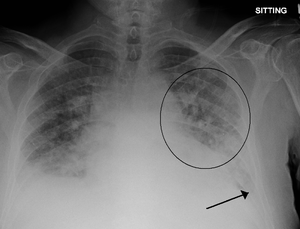

Pulmonary edema with small pleural effusions on both sides.

Kerley B lines in acute cardiac decompensation. The short, horizontal lines can be found everywhere in the right lung.

- CXR

- Cephalization

- Kerley B lines (thick and horizontal)

- Interstitial edema

- Pulmonary venous congestion

- Pleural effusion

- Alveolar edema

- Cardiomegaly